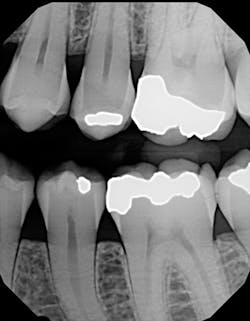

Figure 2: Restored cracked tooth x-ray

I used it on an elusive cracked tooth case. For once, I could actually see the fracture on an x-ray (figure 1). The noted distal fracture caused a great deal of biting pain for this patient. The one difference I noticed with All-Bond is its application method. Two coats are required and a scrubbing motion is needed during the two-coat process prior to curing. Yes, this is a little more time-consuming, but it did not bother me as much as I thought it might when I initially read the application directions. After I saw the results on the x-ray (figure 2), I knew the thin viscosity did not prohibit any type of condensed end product. The composite material flowed well into the proximal areas, and my patient left with no cracks in No. 19.